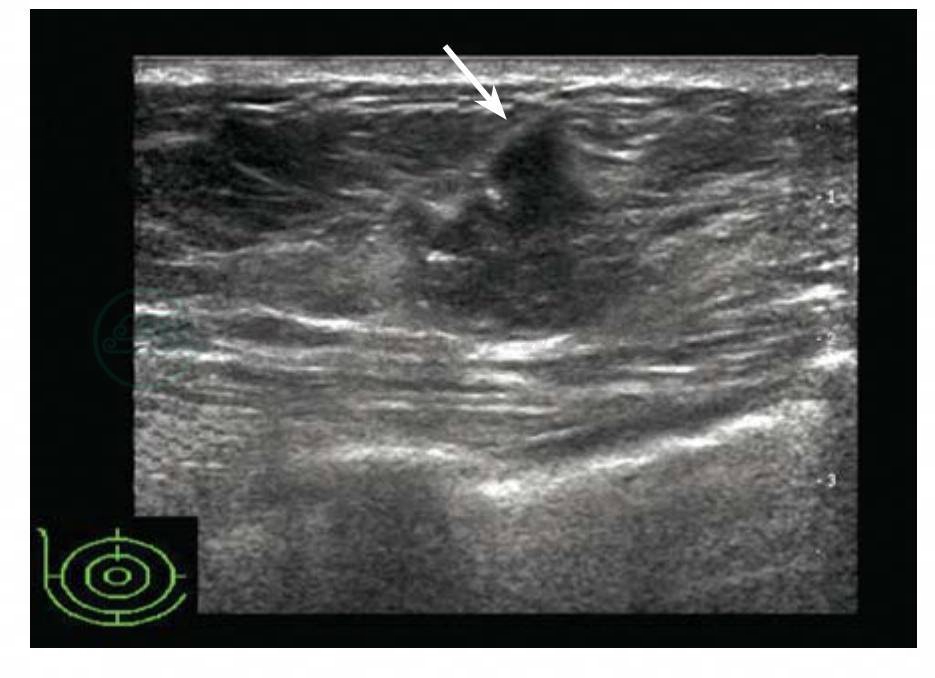

介于皮肤和腺体层之间,除乳头外,腺体层均被脂肪组织覆盖。皮下脂肪厚薄因年龄和肥胖程度差异较大。皮下脂肪呈较低回声,穿行于其间的线状高回声为库柏(Cooper)韧带,一端连于皮肤和浅筋膜浅层,一端连于浅筋膜深层,牵拉乳腺小叶,使腺体表面在韧带附着处不平整略呈波浪形。库柏韧带将皮下脂肪分隔为结节样低回声结构,检查时需注意观察,勿误认为肿瘤。库柏韧带通常在老年女性容易显示(图5-3),青春期由于皮下脂肪菲薄而不易显示。皮下脂肪可呈条状或团状伸入腺体内,腺体内可以存在局灶性脂肪团,需要注意与瘤样病变鉴别。加压探头,脂肪容易受压变形,可作为重要的鉴别方法。

图5-3 库柏韧带

库柏韧带表现为穿行于皮下脂肪层的线状强回声,连接皮肤和浅筋膜浅层表现为穿行于皮下脂肪层的线状强回声,连接皮肤和浅筋膜浅层